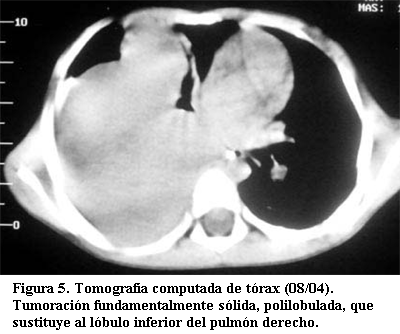

Tomografía computada (30 de agosto de 2004) (figuras 5 y 6): hemitórax derecho: presenta una tumoración fundamentalmente sólida, con áreas quísticas y/o necróticas, que sustituye al lóbulo inferior. La misma desplaza la carina y el bronquio fuente hacia delante y el hígado caudalmente. Existe un pequeño derrame pleural ipsilateral. No hay adenomegalias mediastinales ni abdominales. Hígado de densidad homogénea, sin secundarismo. Bazo, páncreas y riñones sin particularidades.